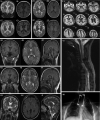

Aminoacyl-tRNA synthetases (ARSs) are ubiquitous, ancient enzymes that charge amino acids to cognate tRNA molecules, the essential first step of protein translation. Here, we describe 32 individuals from 21 families, presenting with microcephaly, neurodevelopmental delay, seizures, peripheral neuropathy, and ataxia, with de novo heterozygous and bi-allelic mutations in asparaginyl-tRNA synthetase (NARS1). We demonstrate a reduction in NARS1 mRNA expression as well as in NARS1 enzyme levels and activity in both individual fibroblasts and induced neural progenitor cells (iNPCs). Molecular modeling of the recessive c.1633C>T (p.Arg545Cys) variant shows weaker spatial positioning and tRNA selectivity. We conclude that de novo and bi-allelic mutations in NARS1 are a significant cause of neurodevelopmental disease, where the mechanism for de novo variants could be toxic gain-of-function and for recessive variants, partial loss-of-function.